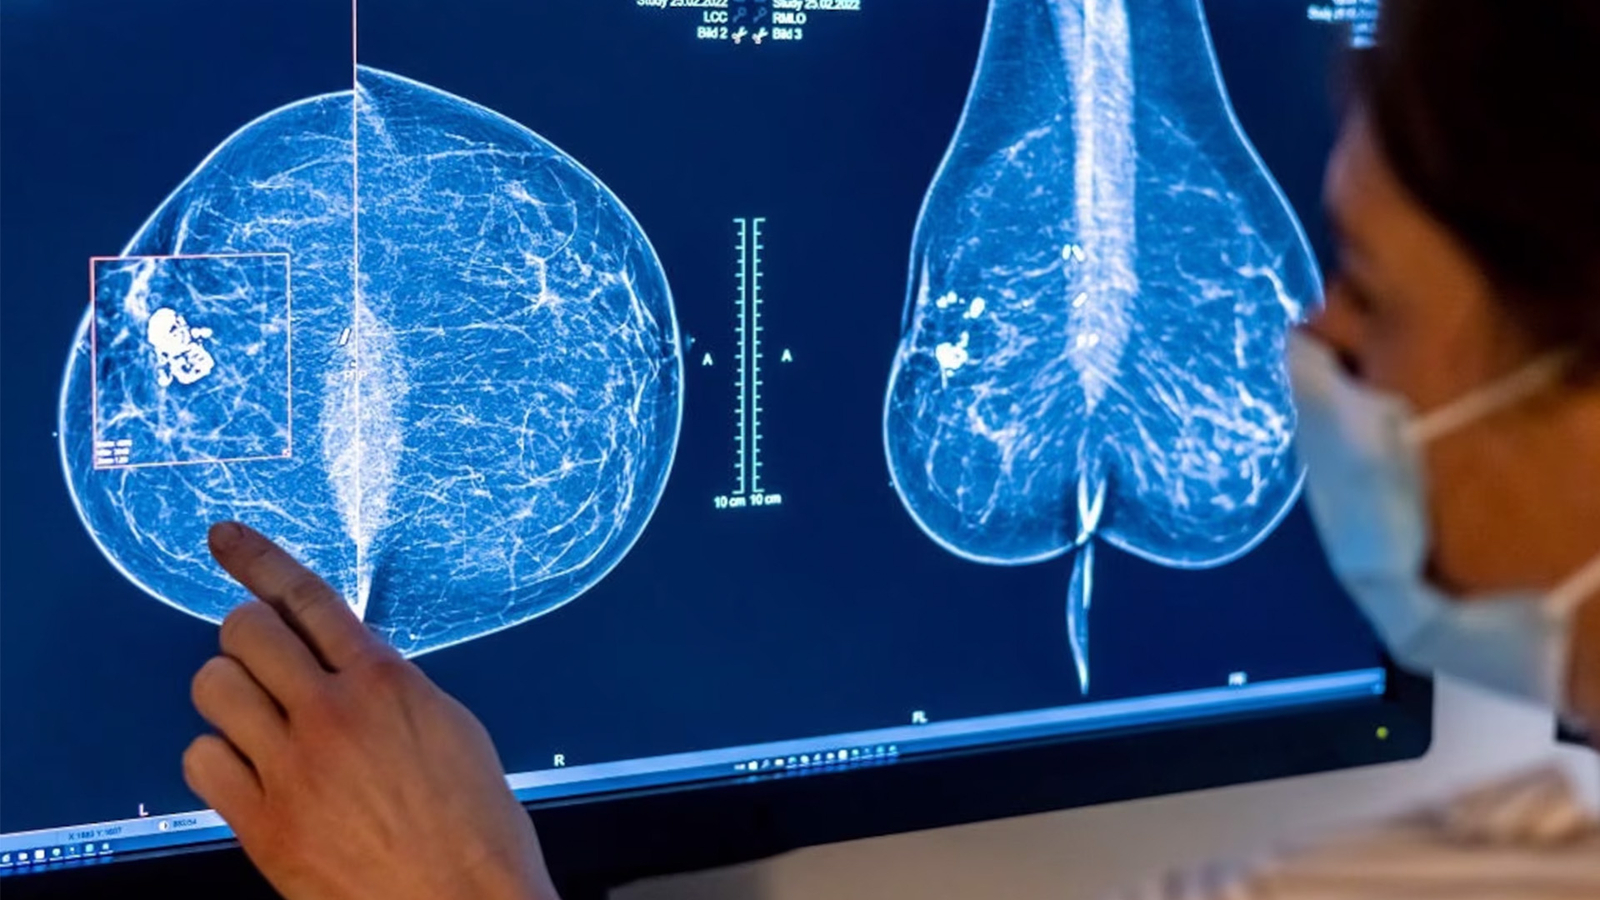

When the results of her routine mammogram came back with a diagnosis of stage 0 DCIS breast cancer in multiple areas of her right breast, Athaliah McPherson, a hairstylist and mom of one, said she wasn't surprised.

McPherson's diagnosis was not life-threatening in and of itself, but left unchecked, it might have developed into something more serious. Typically, doctors treat DCIS with partial or full breast removal surgery, sometimes followed by radiation or hormone therapy to lower future risk.